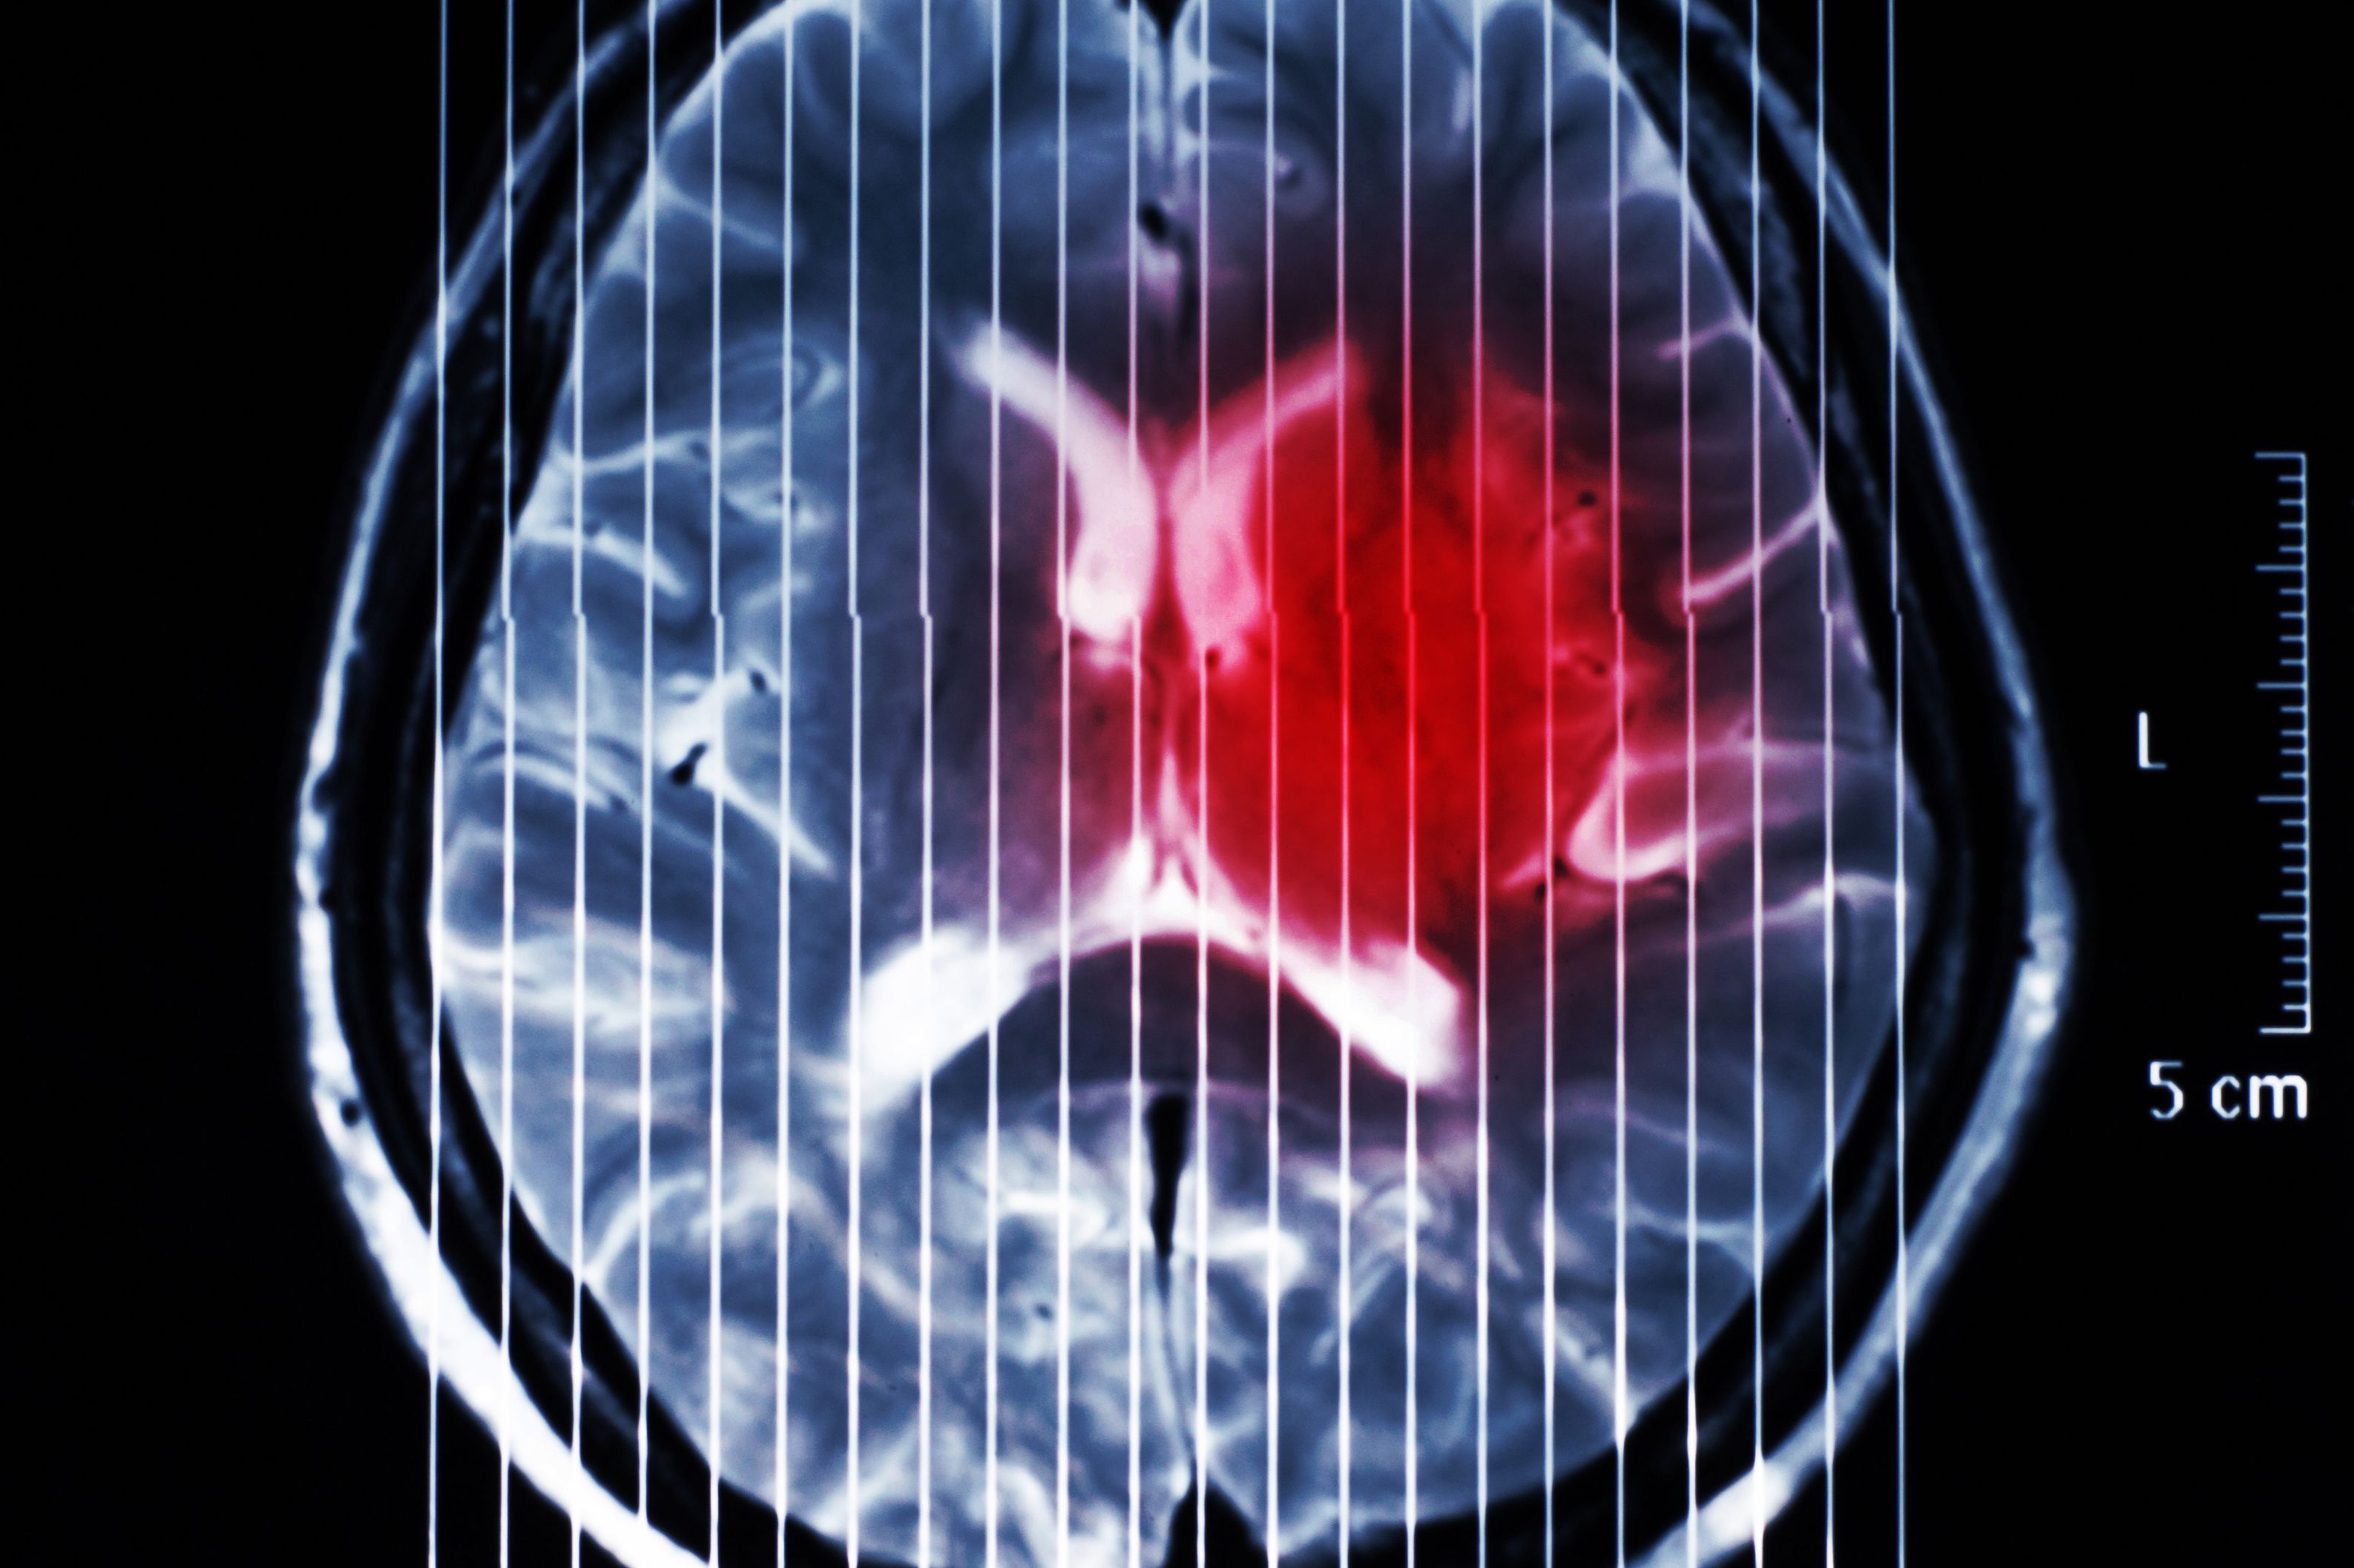

(Wien, 17-12-2024) Das diffuse hemisphärische Gliom (DHG) ist eine Gehirntumorerkrankung bei Kindern, Jugendlichen und jungen Erwachsenen mit einer Überlebensprognose von durchschnittlich weniger als zwei Jahren und eingeschränkten Therapieoptionen. Ein Forschungsteam von MedUni Wien und AKH Wien identifizierte erhöhten Stress durch gezielte Erbsubstanz-(DNA)-Brüche unter gleichzeitiger Hemmung der DNA-Reparatur in der Tumorzelle als vielversprechenden Therapieansatz. Die Studie ist aktuell im Fachjournal „Neuro-Oncology“ erschienen.

Die zugrundeliegenden molekularen Mechanismen des DHG wurden erstmals vor gut zehn Jahren charakterisiert. Das DHG wird aufgrund dieser spezifischen Charakteristika mittlerweile als eigenständige Hirntumorart gelistet. Bisher konnte dieses Wissen aber nicht in effizientere Therapiemöglichkeiten umgesetzt werden. Die aktuelle Forschungsarbeit unter der Leitung von Johannes Gojo (Universitätsklinik für Kinder- und Jugendheilkunde) und Walter Berger (Zentrum für Krebsforschung) konnte zeigen, dass die Tumorzellen einen speziellen Mechanismus nutzen, um „unsterblich“ zu werden. Dieser Mechanismus geht aber mit erhöhtem Stress aufgrund von vermehrten Erbsubstanz (DNA)-Schäden einher. Diese „Verletzlichkeit“ identifizierte die Forschungsgruppe als neuen therapeutischen Ansatz und zeigte, dass das gezielte Auslösen weiterer DNA-Schäden unter gleichzeitiger Hemmung der DNA-Reparatur einen vielversprechenden Therapieansatz für diese aggressive Tumorart des Gehirns darstellt.